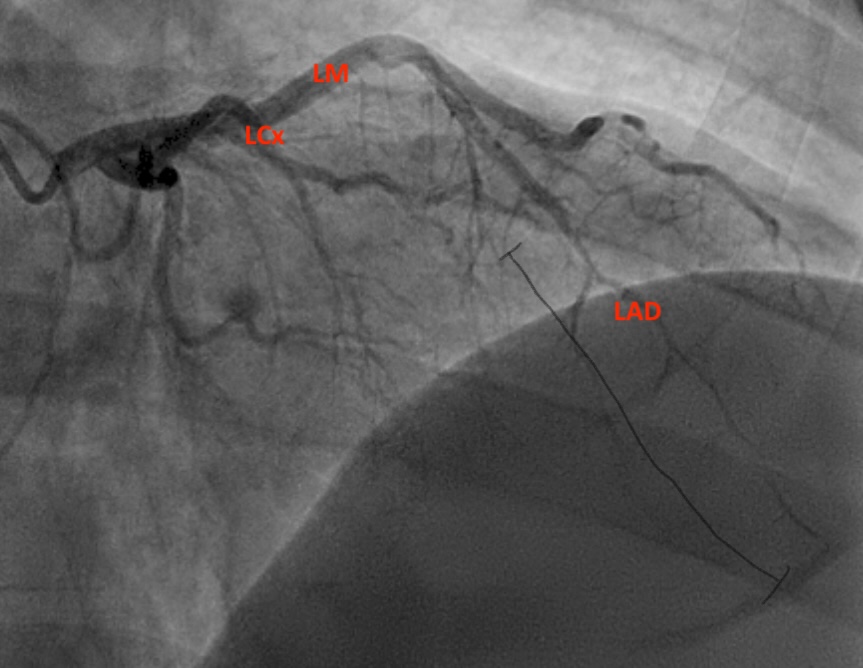

This case report discusses a 36-year-old male who presented to the emergency department with an atypical story for acute coronary syndrome (ACS). Initially, the patient was felt to have a non-diagnostic electrocardiogram (ECG). Once the laboratory test results were obtained and the initial high-sensitivity troponin was noted to be elevated, the initial ECG was again reviewed. The patient was felt this time to have an abnormal ECG, demonstrating borderline ST elevation in leads I, aVL, and V2-V5. The interventional cardiologist on call was contacted, and the cardiac catheterization lab was activated. Upon left heart catheterization, the patient was found to have a spontaneous coronary artery dissection (SCAD) of the distal left anterior descending (LAD) artery. Post-catheterization, the patient was observed on cardiac telemetry and started on dual antiplatelet therapy. Echocardiogram revealed a preserved ejection fraction (EF), but hypokinesis of the apical anterior, anterolateral, inferior, and apical myocardium. The patient was discharged within 48 hours without any complications.